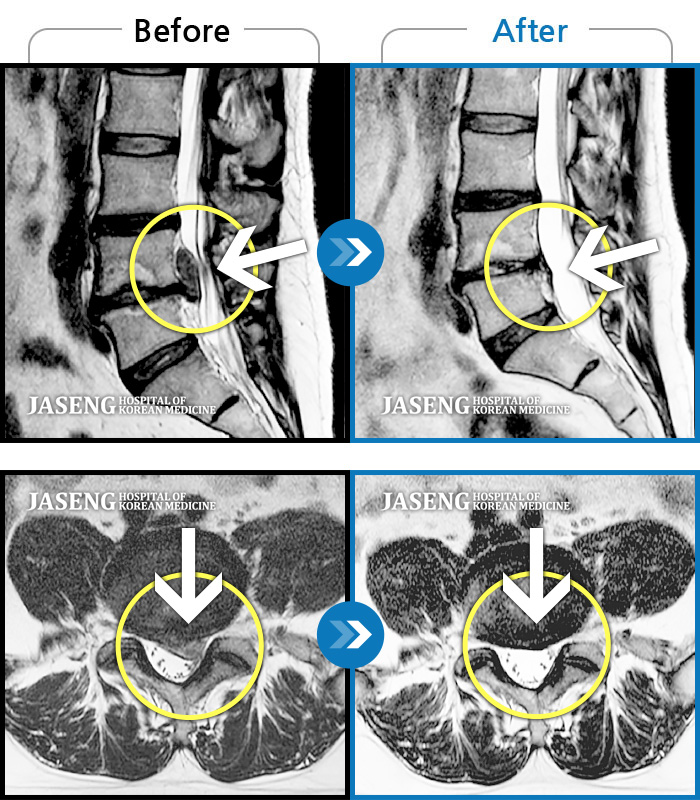

- 척추관협착증

서울의 모 대학 병원에서 디스크 수술의 받으시고 1년 만에 다시 마비가 와서 불안한 마음으로 재수술

을 준비 하던 중에 세미급 병원 이사님으로 계시는 지인 분께서 강남 자생의 이진호 원장님을 추천 주셔서 수술 전에 반신반의 하는 마음으로 찾아 뵈었습니다.

왜 진작에 이진호 원장님을 찾아 뵙지 않았는지...정말 후회 합니다. 외과적 수술 전에 찾아 뵈었으면 나이 드신 어머니가 고생하지 않으시고 편안한 환경, 나이스한 성격에 유능하시고 환자의 치료에 진심이신 원장님의 치료를 받으며 완쾌하셨을 터인데... 아들로써 그동안 어머님께 무관심했던 것 아닌가 이진호 원장님의 치료를 받으며 하루 하루가 다르게 상태가 호전되어가는 어머님의 허리를 보며 마음이 무거웠습니다. 이진호 원장님께 무한한 감사를 드리며 글을 올립니다. 최고의 명의 이진호 원장님 정말 감사드립니다. -

저는. 1919. 9월부터 12. 월 31 일 까지 척추관. 협착증 임상에. 참가했습니다~ 삶에 쫒기다 보니 재대로 치료도. 못하고 다 망가져 버린. 제 몸을 이진호 원장님께서 자생에 가장좋은. 기술과. 최상의. 서비스로 저 같은 사람에게 치료의 기회를 주셔서. 정말. 감사 했습니다~ 경자년 새해에도. 더 건강하시고 더. 많은 사람에게. 등불을.밝혀줄 이진호 원장님 존경하고. 많이. 칭찬 합니다~~♡